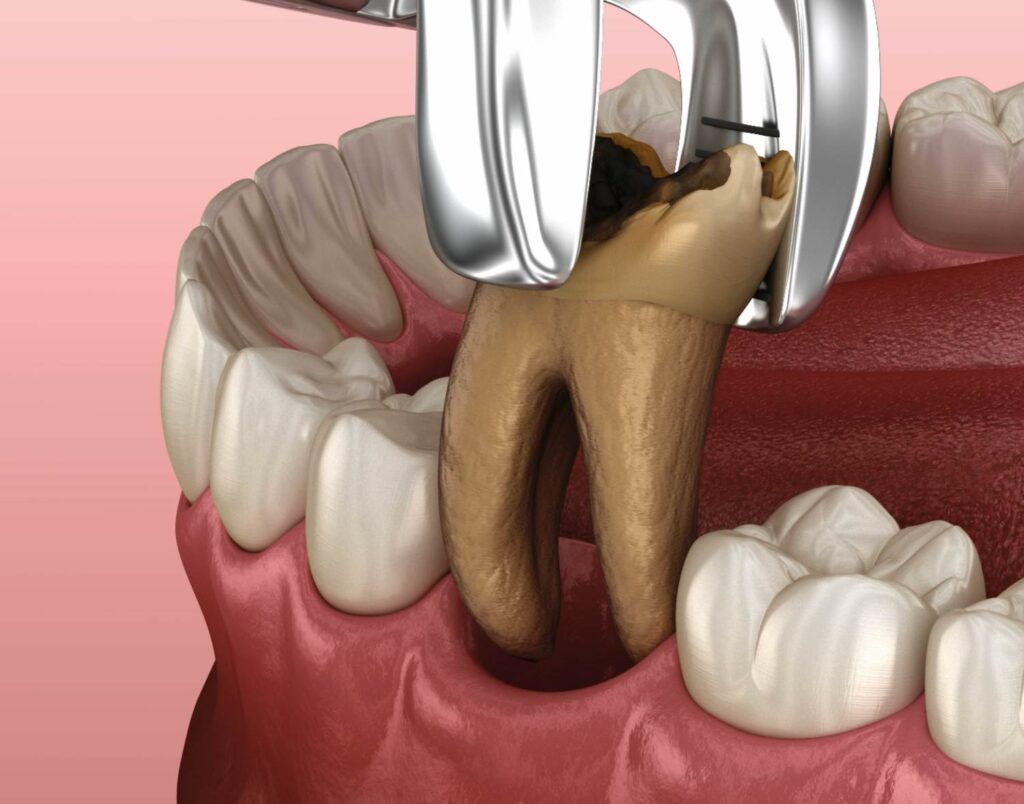

Ekstrakcje zębów

Przeprowadzamy zabiegi usunięcia zębów zatrzymanych, uszkodzonych, zainfekowanych czy zębów, które bywają przyczyną problemów ortodontycznych. Najczęściej wykonuje się ekstrakcje zębów mądrości, czyli tzw. ósemek.